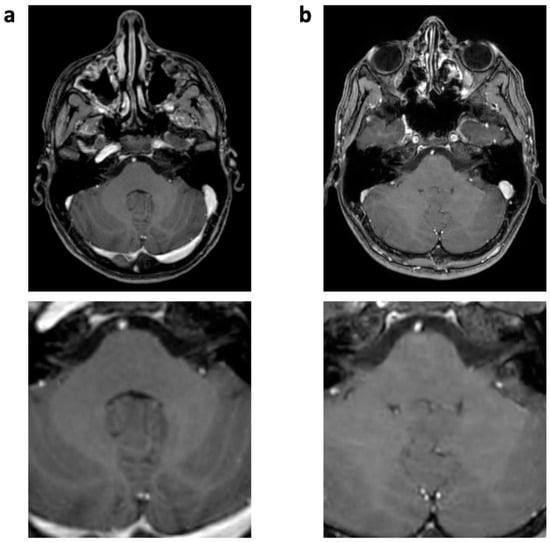

Figure 6.

FLAIR images of a 5-year-old male patient with astrocytoma (post-resection). Bright CSF-flow-related enhancement (FRE, arrowheads) in fourth ventricle and prepontine cisterns is seen in SENSE FLAIR (a), not present in CS FLAIR (b). As a consequence, the CSF-dependent ghosting artifacts (arrow) did not occur.